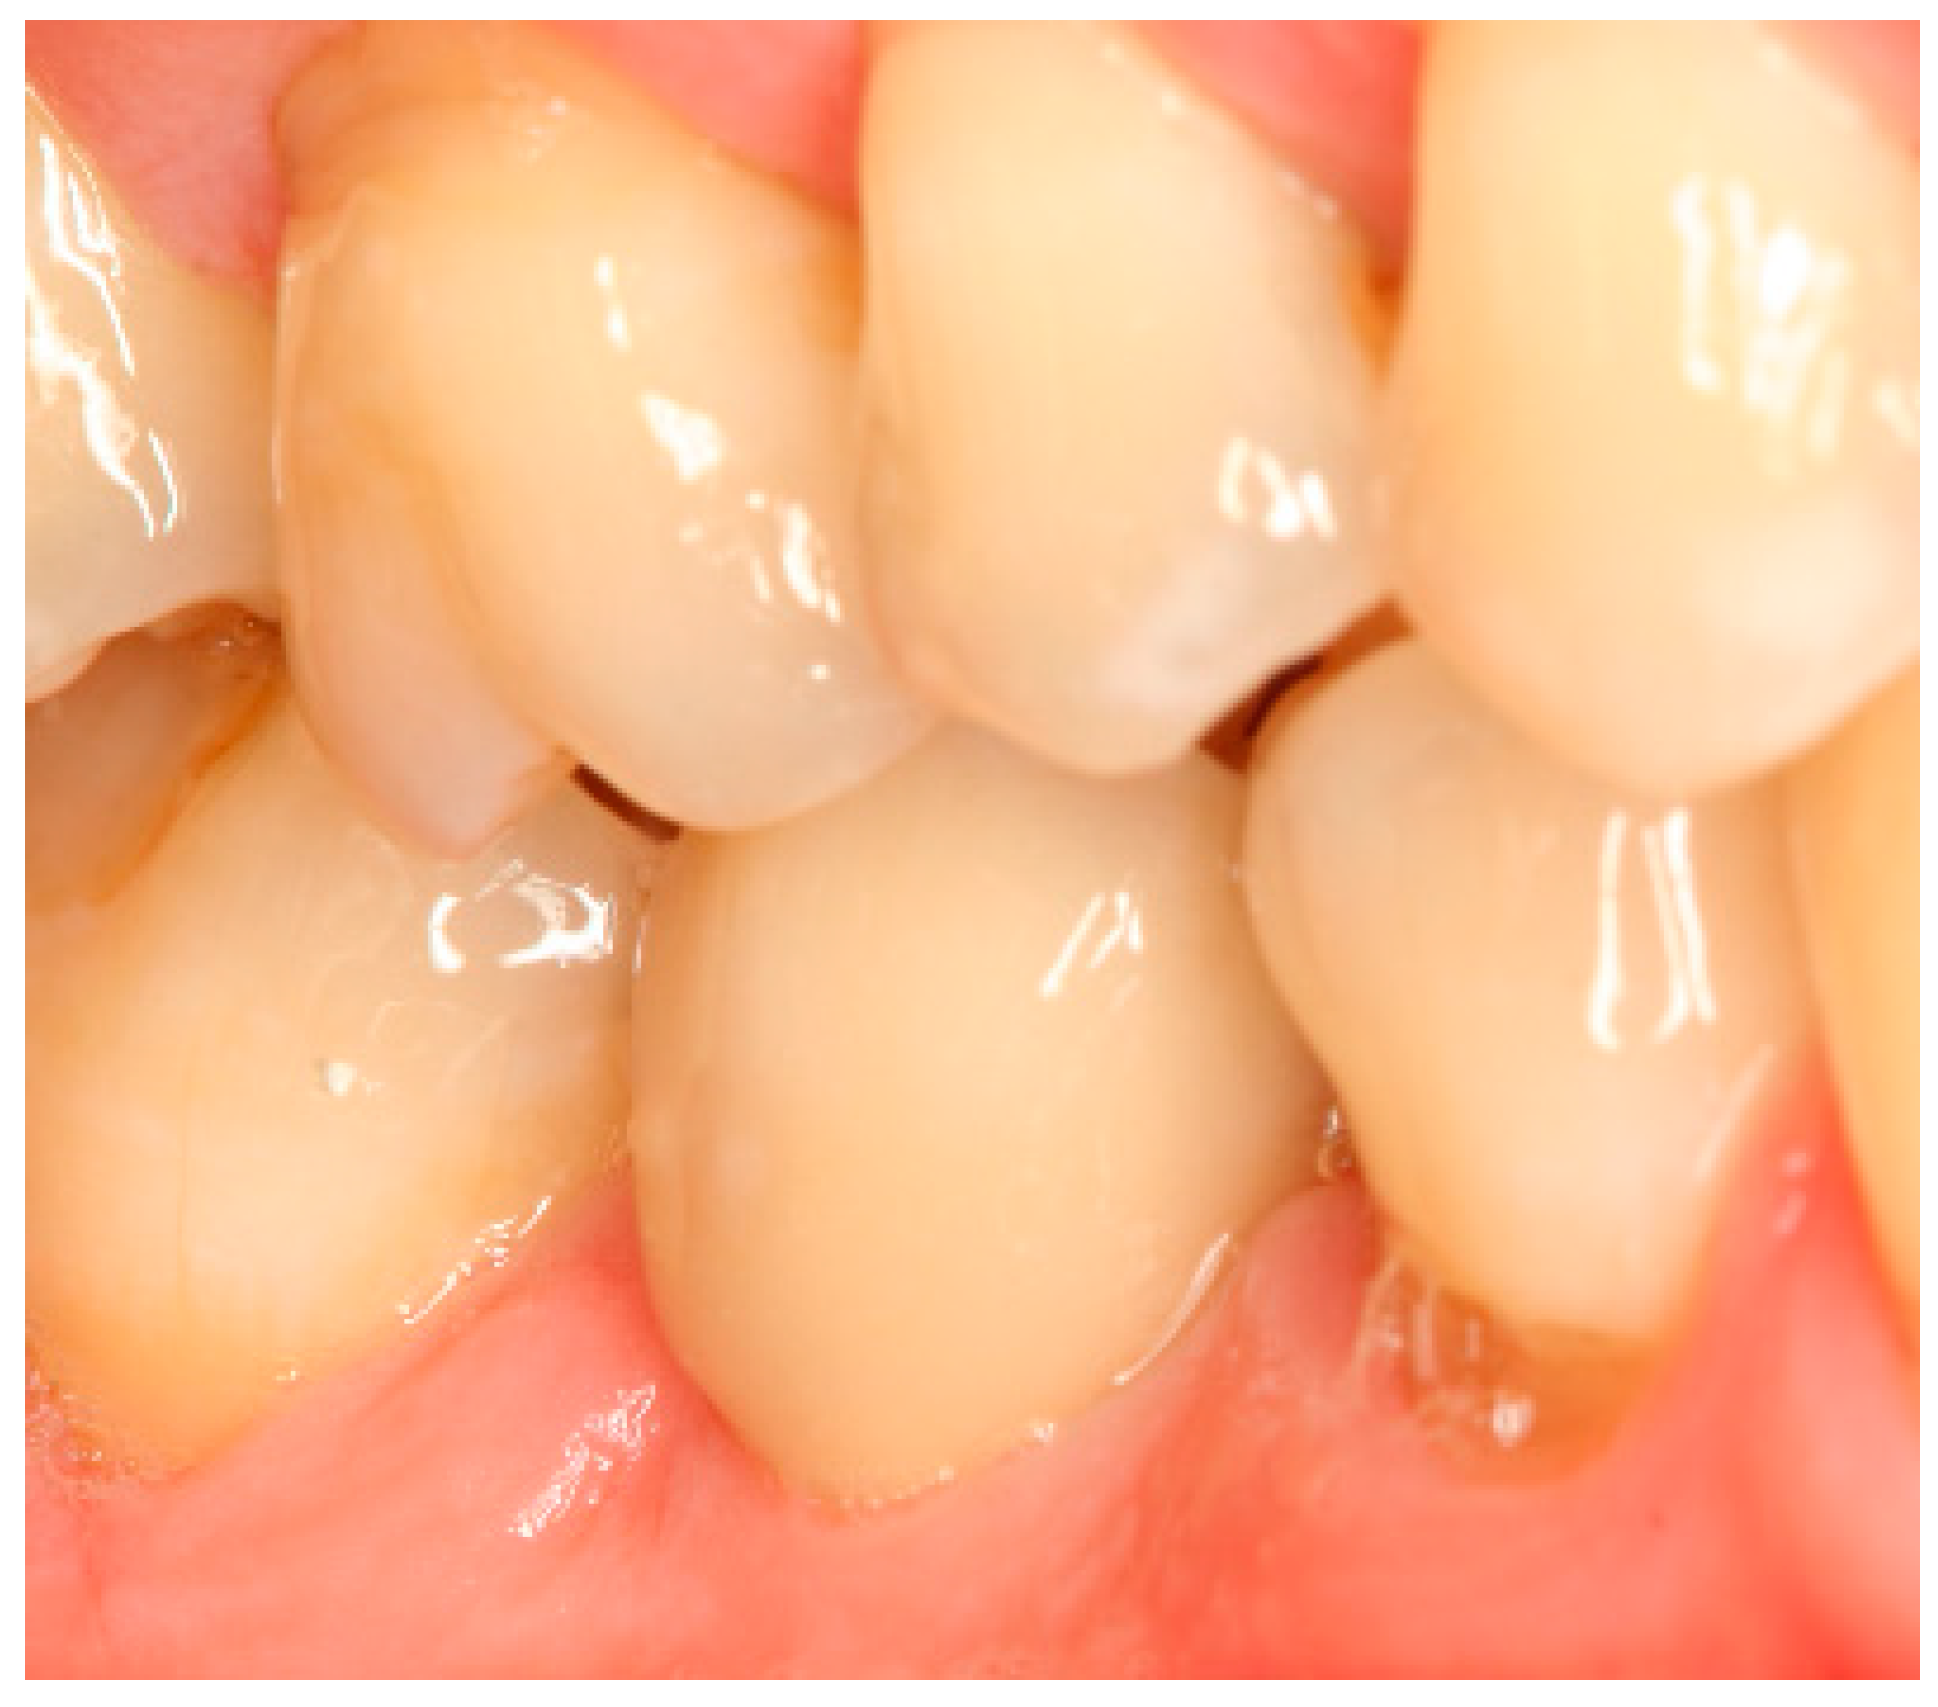

Situation after crown cementation. Lateral view.

Clinical situation at the 1-year follow-up. Lateral view.

Clinical situation at the 3-year follow-up. Lateral view.

Clinical situation at the 5-year follow-up. Lateral view.